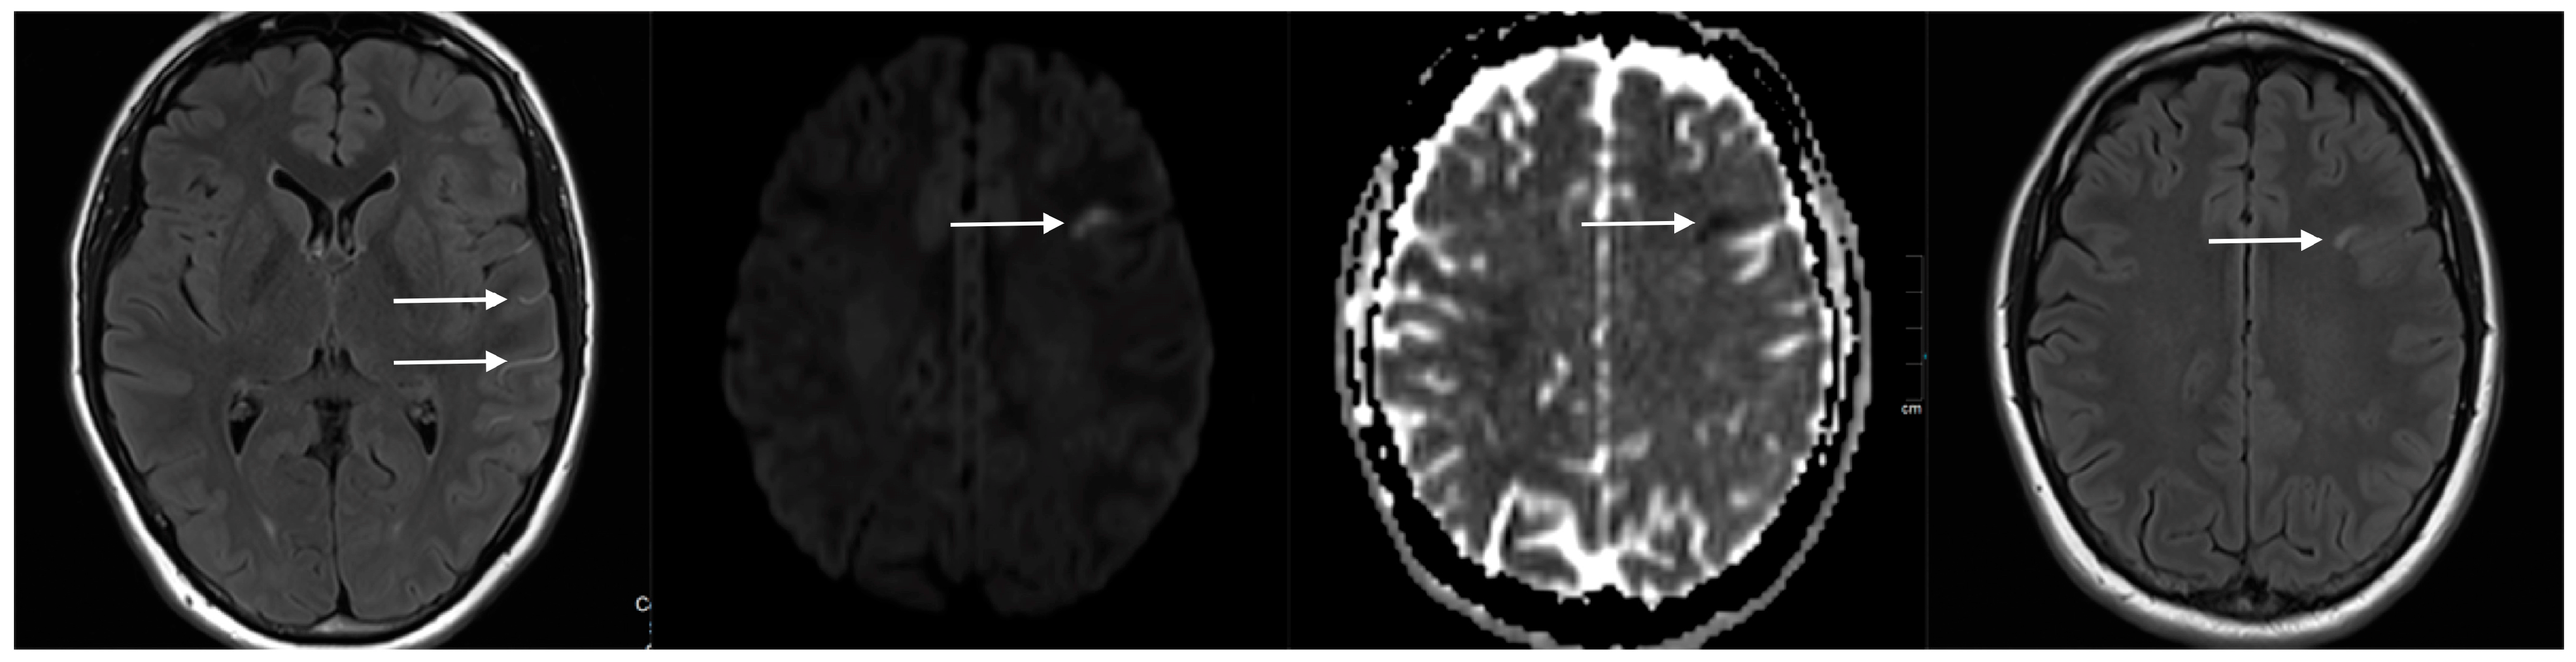

| 27 | Female | 27 | Left M1, ruptured saccular aneurysm, P&P | 3.5 | 2.8 | SVB 3.25 × 20 | 0.45 mm, 16% | >85% of the proximal (ICA) and >60% of the distal landing zone (M1) | 3 weeks | 10% | >95% |